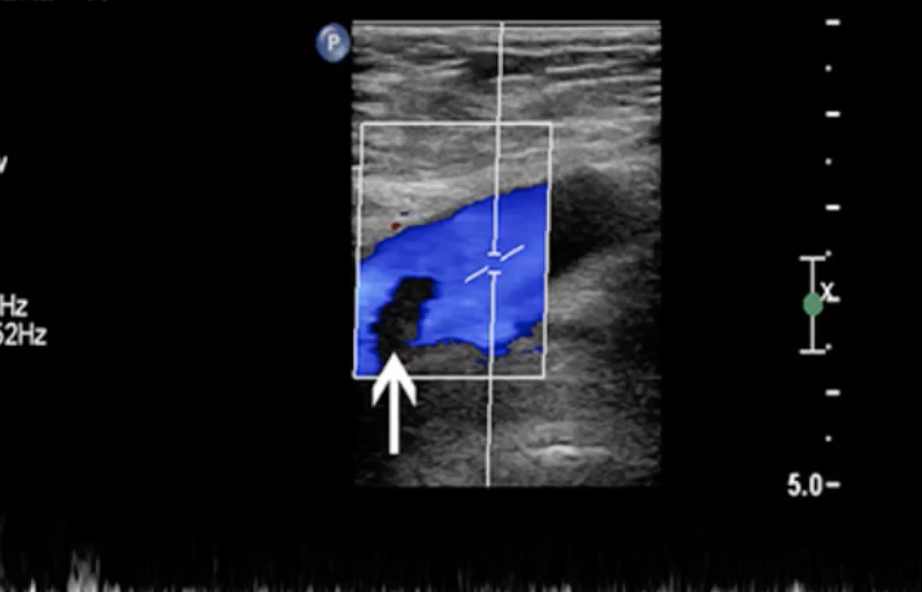

If a patient has had a d-dimer test and a Wells Score calculated and you are still unsure if the patient has a DVT, what imaging technology can you use?